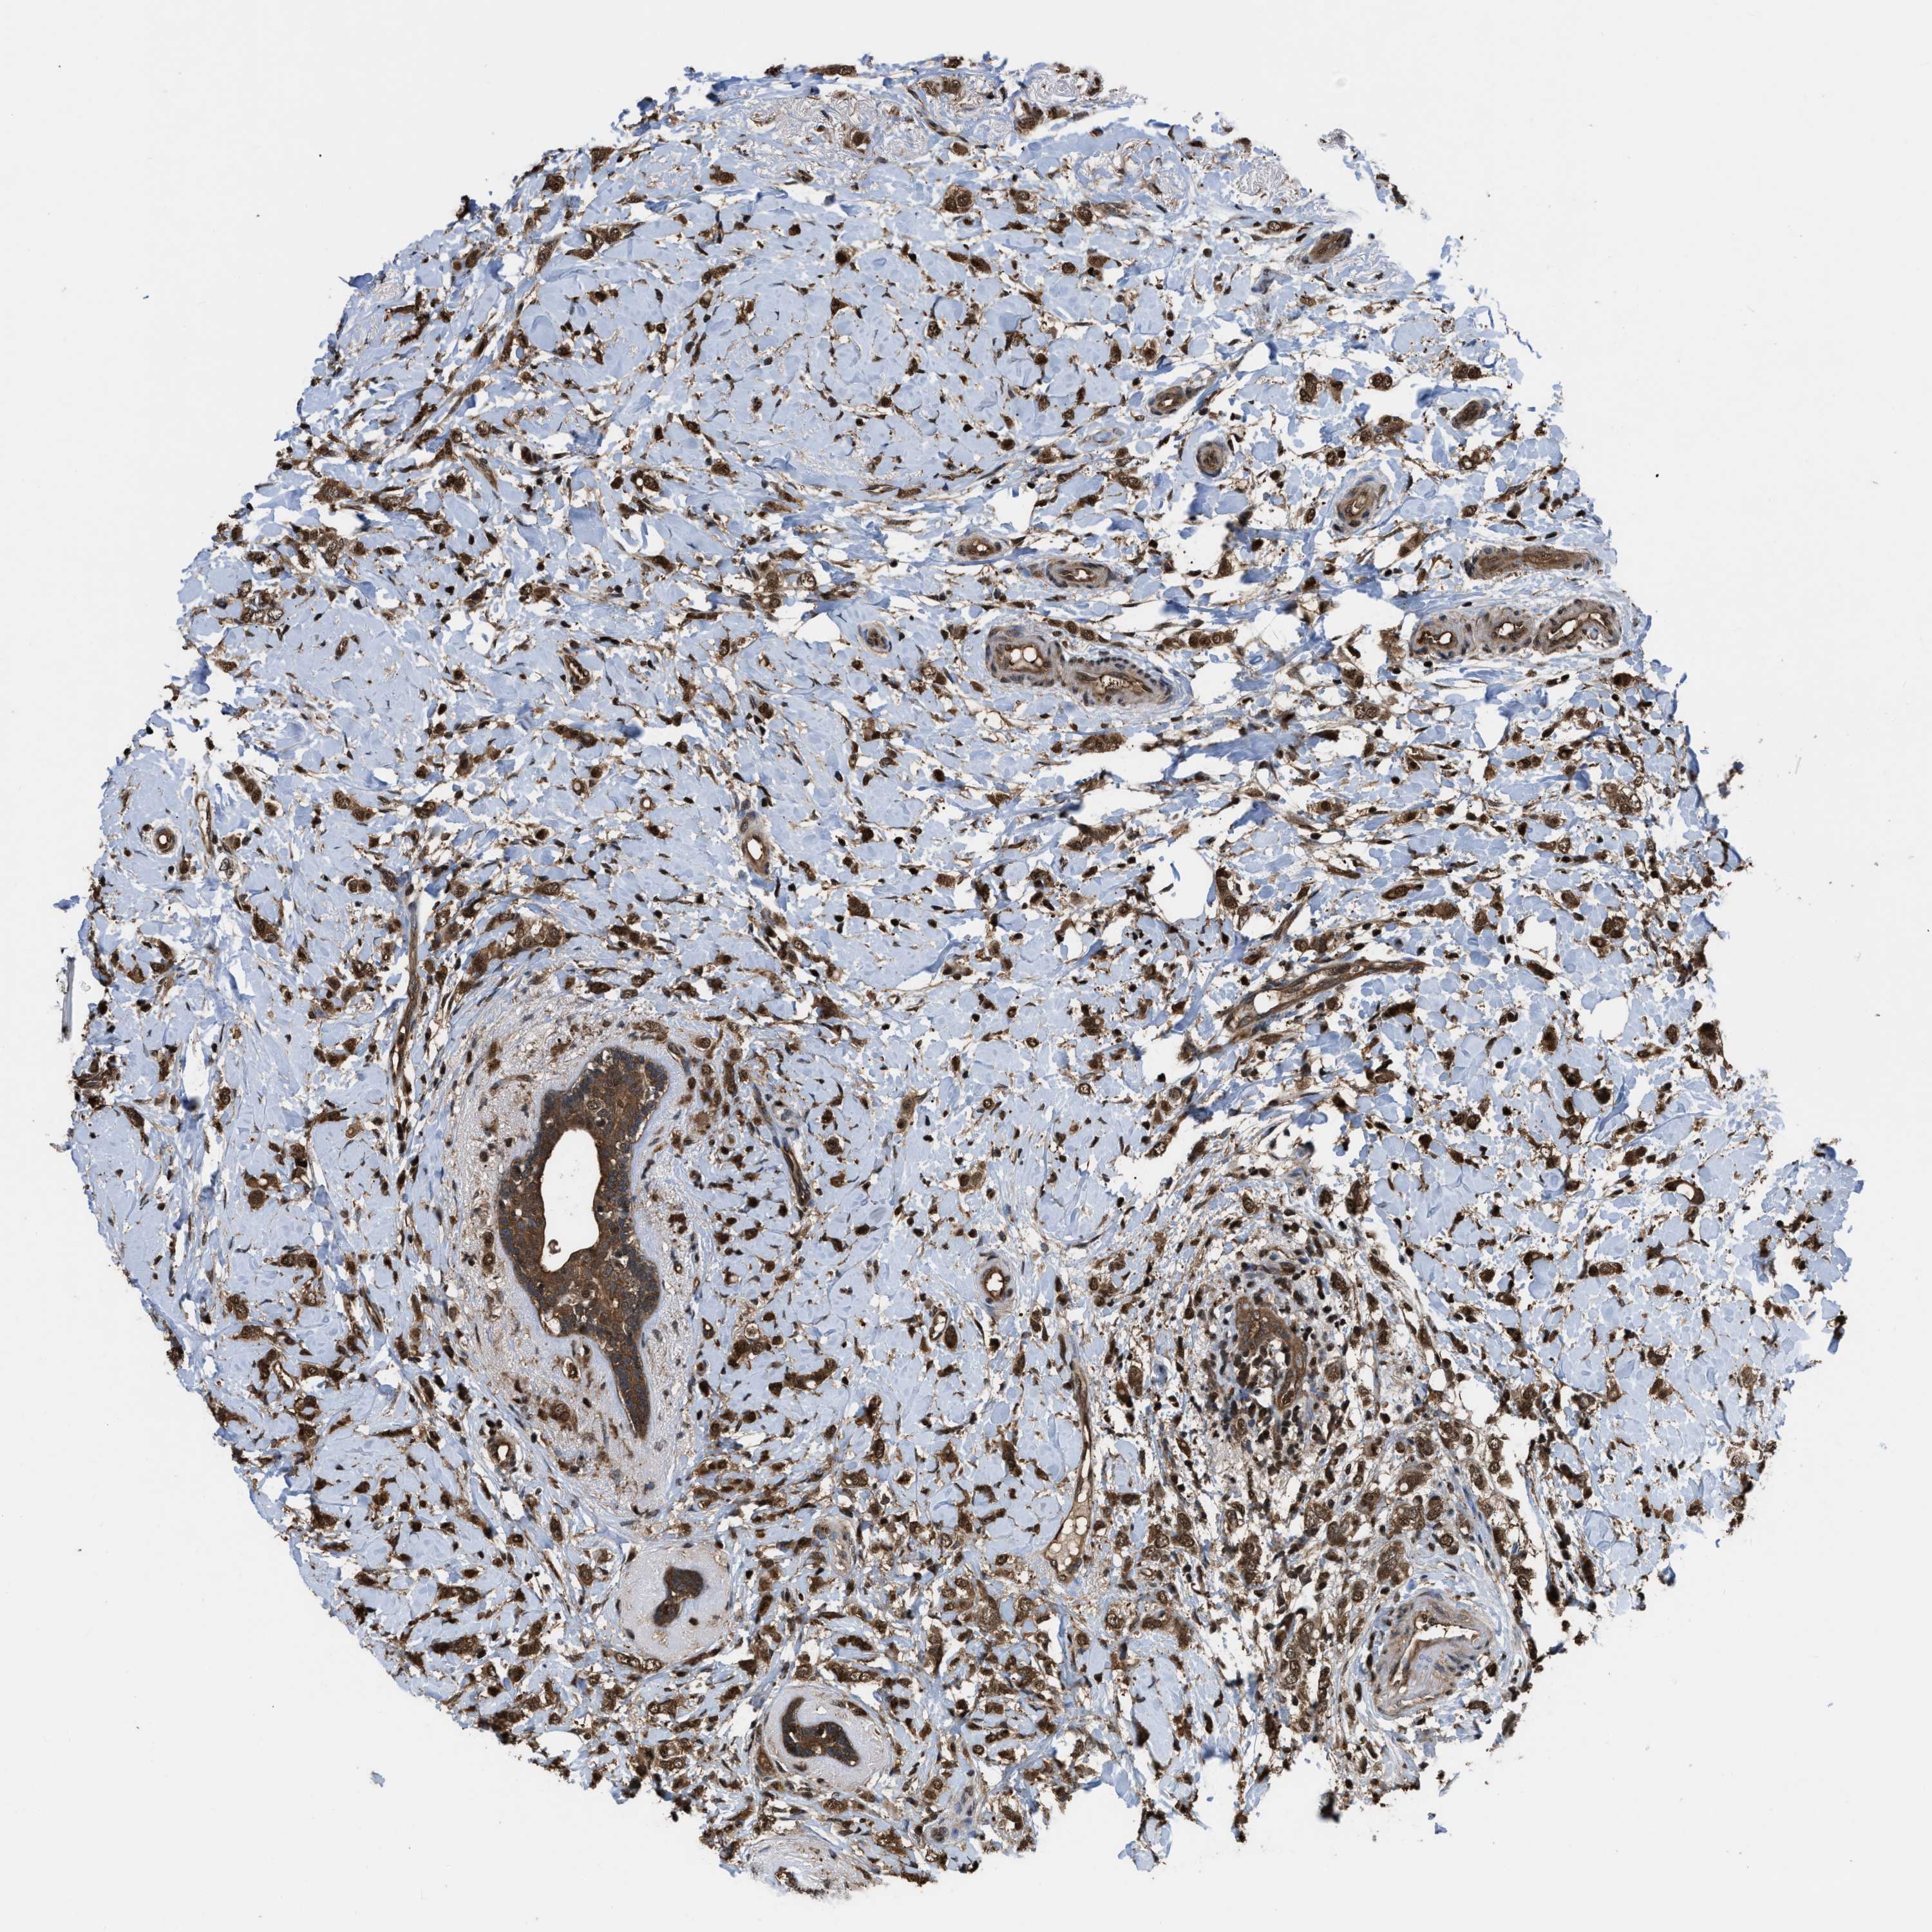

CANCER BREAST CANCER Show tissue menu

BRCA TCGA BRCA VALIDATION PROTEIN EXPRESSION

ANTIBODIES